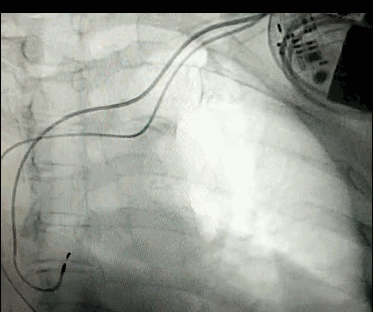

腦血管成像的“金標準”!——DSA三部曲之技術(shù)篇

DSA是將造影劑注入需要檢查的血管中,使血管顯露原形,然后通過系統(tǒng)處理,使血管顯示更加清晰,便于醫(yī)生診斷或進行手術(shù)。